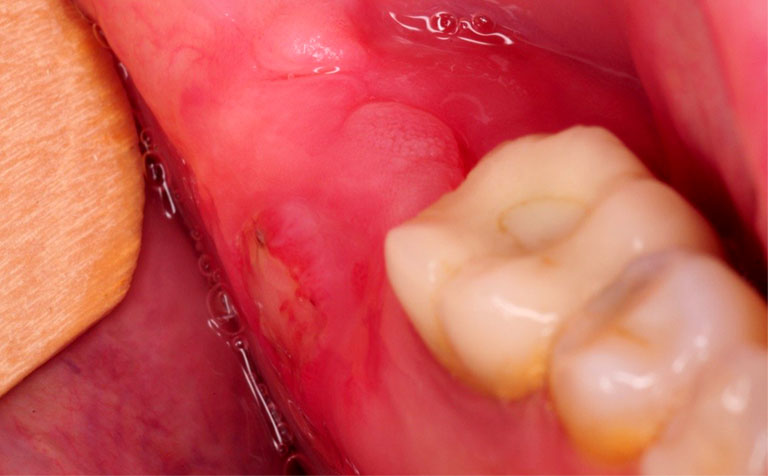

Nhổ răng khôn ở đâu an toàn tại quận Thanh Xuân Hà Nội